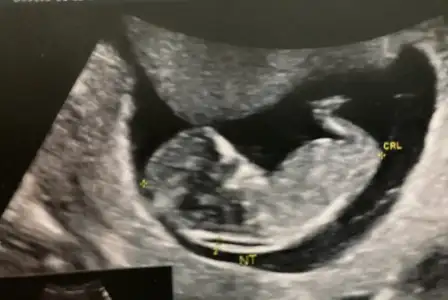

11+0 günlük. cinsiyet tahmininiz var mı acaba?

• WhatsApp Image 2021-12-22 at 11.31.30.webp

WhatsApp Image 2021-12-22 at 11.31.30.webp

44,5 KB · Görüntüleme: 79

• InkedWhatsApp Image 2021-12-22 at 11.25.21_LI.webp

InkedWhatsApp Image 2021-12-22 at 11.25.21_LI.webp

19,4 KB · Görüntüleme: 79